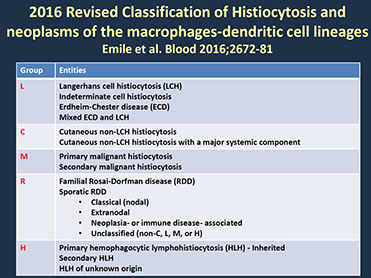

Histiocytic and dendritic cell neoplasms

Hemophagocytic Lymphohistiocytosis, Rosai-Dorfman disease (see Spleen and Lymph Node)

Histiocytic sarcoma

Tumors derived from Langerhans cells

- Langerhans cell histiocytosis (LCH)

- Langerhans cell sarcoma (LCS)

Indeterminate dendritic cell tumor

Interdigitating dendritic cell sarcoma

Follicular dendritic cell sarcoma

- Inflammatory pseudotumour-like follicular/fibroblastic dendritic cell sarcoma

Fibroblastic reticular cell tumor

Disseminated juvenile xanthogranuloma

Erdheim-Chester disease